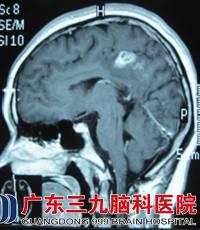

小邓,19岁,右手发作性抽搐已有15年,通过检查,CT及MRI的结果提示:右侧顶叶深部白质内病灶,血清裂头蚴抗体呈阳性。神经外六科的吴杰主任诊断为:1、症状性癫痫,2、右侧顶叶中央区脑裂头蚴病。

术前颅内影像